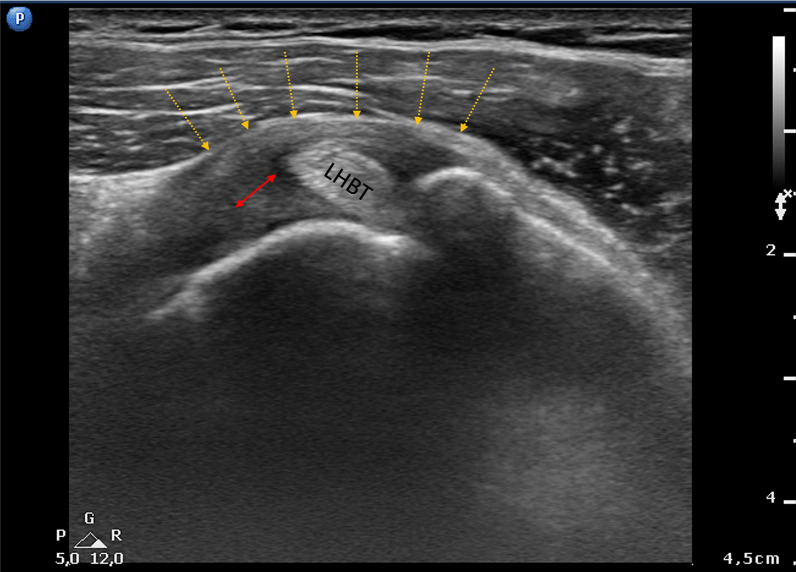

Fig. 5.

Axial section of the normally concave rotator interval showing conspicuous coracohumeral ligament thickening (red double arrow) with a rounded and convex profile (yellow dotted arrows). LHBT long head of the biceps tendon

Seventy-five of the patients with AC (71%) showed ELHBT. Pulley thickening (CHL and/or SGHL) in comparison with the contralateral shoulder was detected in 93 patients (88%): mean thickness 2.3 ± 0.25 mm (1.6–2.7) vs 1 ± 0.11 mm (0.8–1.2); p < 0.0001. This sign had a sensitivity of 88%, a specificity of 52% and a diagnostic accuracy of 54.6%. The pulley was more than 60% thicker than that of the contralateral shoulder in all cases. Of the 93 patients with CHL or SGHL thickening, US showed that the normally concave rotator interval had a rounded and convex profile (Fig. 5) in 38, and a “pseudo-double” tendon appearance of the LHBT in the transverse section of the pulley in 43 (Fig. 6). The smaller false tendon was the CHL if it was lateral to the LHBT, and the SGHL if it was medial.